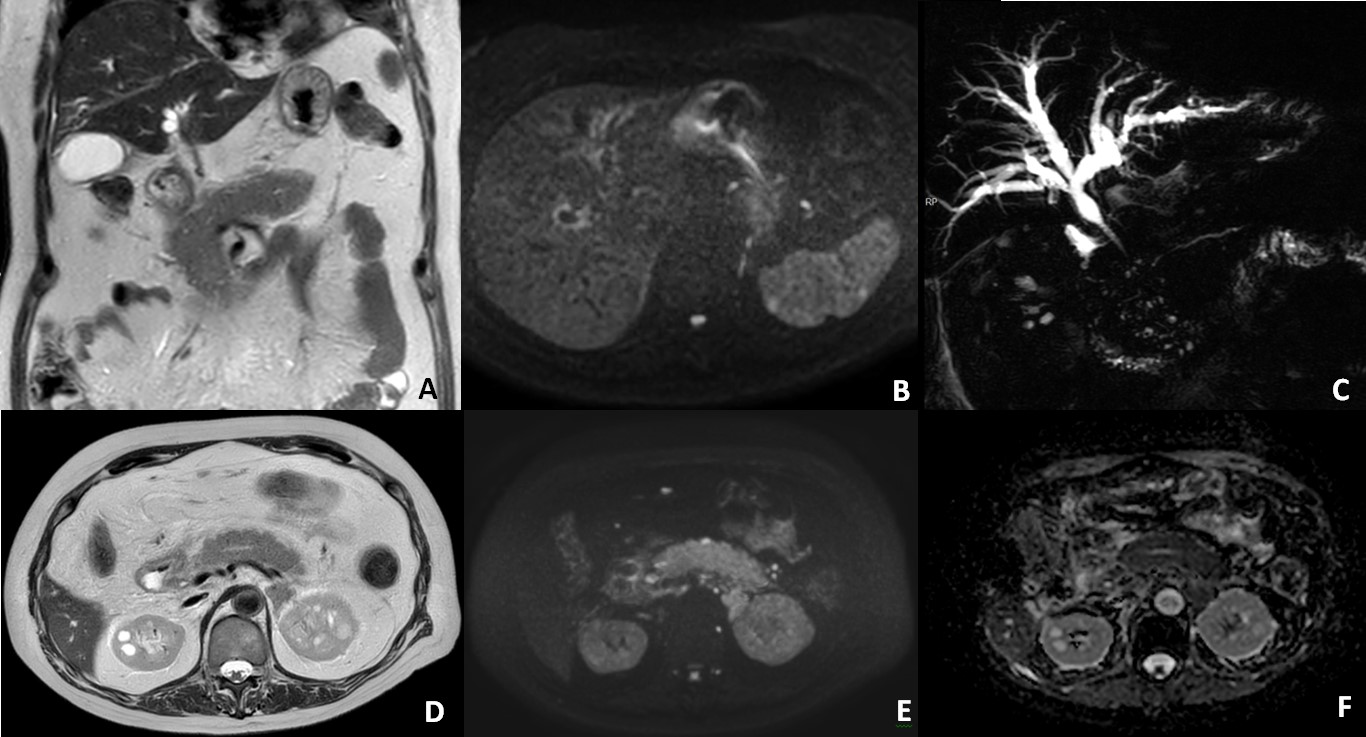

The CT scan revealed diffuse dilatation of intra-hepatic biliary ducts (Figure 1A). Diffuse enlargement of the pancreas and peri-pancreatic fat stranding were also noted, suggesting inflammatory pattern (Figure 1B-C). Alongside dilatation of intra-hepatic bile ducts, the MRI scan showed a long stricture of the common bile duct (Figure 2A, 2C). Increased wall thickness of the common bile duct was also observed (Figure 2A).

Figure 1: Abdominal CT (A, B) axial portal-phase and (C, D) coronal portal-phase, demonstrating diffuse intra-hepatic bile duct dilatation (A) and diffuse enlargement of the pancreas (B, C) and peri-pancreatic fat stranding (D).

In the present case, diffuse pancreatic enlargement was observed with peri-pancreatic fat stranding (Figure 1B-D; Figure 2D), along with restricted diffusion, suggesting inflammatory pattern. Additionally, diffuse intrahepatic and focal extrahepatic bile duct dilatation were observed (Figure 2C), with diffuse thickening of the extrahepatic bile duct wall and of the gallbladder wall (Figure 2A). These findings suggest concomitant ICI-induced cholangitis.